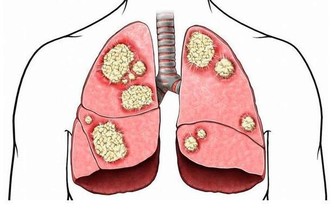

許多研究發現,日常生活中最為常見食物——番茄,有抗列腺癌的效果。因此,平時適量吃點,不僅能補充維生素,還能抵御前列腺癌,好處多。

很多人都知道換都有植物雌激素,能惠澤女性,滋養身體,但實際上,黃豆對男性也有好處。據資料顯示,常吃黃豆製品的男人,患上前列腺癌的概率要比極少吃黃豆製品的男人要低。

胡蘿蔔被認為是對抗前列腺癌的“小尖兵”。有研究指出,體內β胡蘿蔔素濃度高的人和較低者相比,患上前列腺癌的機率要低許多。胡蘿蔔素含有較多的營養物質,能補充身體日常所需要的營養物質,還可以降低患上心血患疾病的風險。